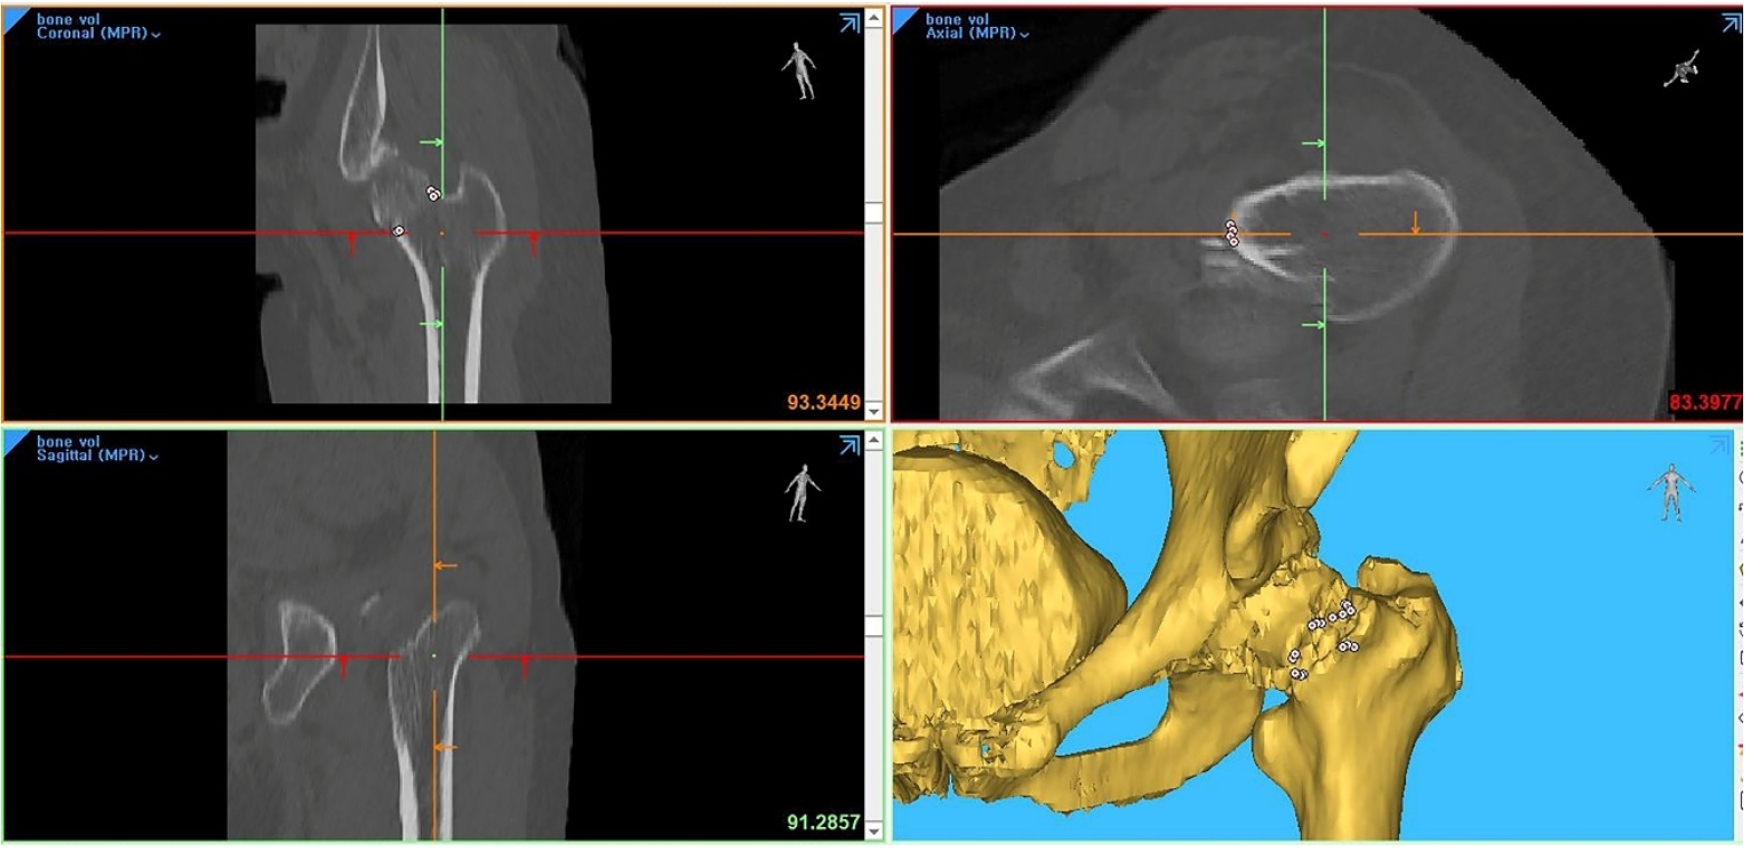

Three-dimensional computed tomography-based differentiation of engaged versus displaced intertrochanteric fractures using the anterior fracture line: a cross-sectional study from Korea

Jae-Suk Chang, Jin Yeob Park, Sang-Ok Chun, Chul-Ho Kim

J Musculoskelet Trauma 2026;39(1):30-37.

Jae-Suk Chang, Jin Yeob Park, Sang-Ok Chun, et al.